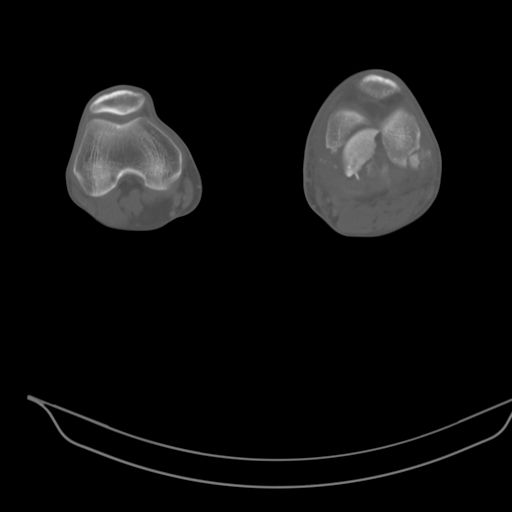

CT shows major bony fragments which are markedly rotated .With this amount of bony damage,you probably should attempt to get reasonably loooking knee with ORIF and thn if he needs a TKR due to pain a few years from now, then tleast you have something looking like a knee that you can replace rather than having to use revision knee for a primary TKR now. 4 weeks is not too long .what is the condition of soft tissues?

При внутрисуcтавных переломах трехмерные (3D) изображения, кроме красивого снимка, не дают полную информацию о состоянии отломков, самыми информативными являются корональные срезы на КТ и обычная длинная ренгенограмма конечности для сравнения оси конечности.